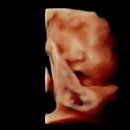

27주!!에 방문하게된 평택 서울유산부인과 주병원은 평택 라움산부인과에요 29주에 입체초음파 찍기로 했지만 너무 궁금해서 동학동 서울유산부인과 방문했어요...왔네요 서울유산부인과의원 경기도 평택시 지제동삭2로 181-26 아드리아메디타워 4층 접수하면서 혈압과 몸무게 적어서 바로 냈어요 평택 임산부 혜택...